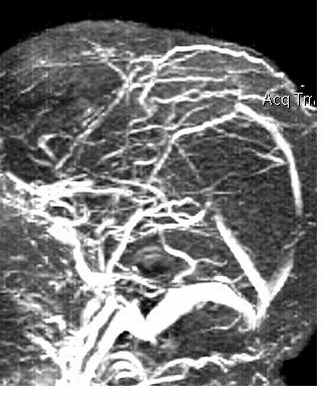

При МРТ головного мозга выявляется образование с широким основанием. Гиперостоз, часто видимый при КТ и на рентгенограммах, при МРТ головного мозга выглядит как утолщение внутренней костной пластинки свода черепа. Кальцинаты, обнаруживаемые при КТ в 20% наблюдений, при МРТ не видны. Опухоль при МРТ довольно однородная по структуре. Прорастание костей свода черепа видно отчетливо как участок повышенного сигнала на МРТ головного мозга любого типа в резко гипоинтенсивной кости. Сигнал от опухолевого узла на Т2-зависимых МРТ зависит от гистологического подтипа: относительно низкой интенсивности (между белым и серым веществом) при фибробластном и высокой при ангиобластном и синтициальном. Отек выражен в различной степени в каждом конкретном случае. Ряд МРТ признаков очень характерен для менингиомы: полоса ликвора между опухолью и тканью мозга, смещение окружающих сосудов. Они отражают неинвазивный характер роста. Смещенную и вовлеченную твердую мозговую оболочку иногда удается визуализировать при МРТ после введения гадолиния, особенно на корональных МРТ срезах. Усиление сигнала при МРТ с контрастированием от оболочки над опухолью с распространением в стороны (симптом “хвоста”) не абсолютно специфично и встречается при МРТ как при менингиоме, так и при лептоменингиальных метастазах. Однако при глиальных опухолях и невриноме при МРТ оно не описано. При обследовании пациентов методом МРТ в СПб с менингиомами серпа (фалькс-менингиомы) и намёта мозжечка рекомендуется делать МР-венографию для определения компрессии синуса и его проходимости. В наших центрах это обязательное исследование перед операцией. На открытом МРТ венография также легко выполнима. Не все центры МРТ СПб придерживаются этой методики.

МРТ головного мозга. Менингиома верхнего сагиттального синуса. Аксиальная Т2-взвешенная МРТ и сагиттальная Т1-взвешенная МРТ и сагиттальная МР-венограмма.